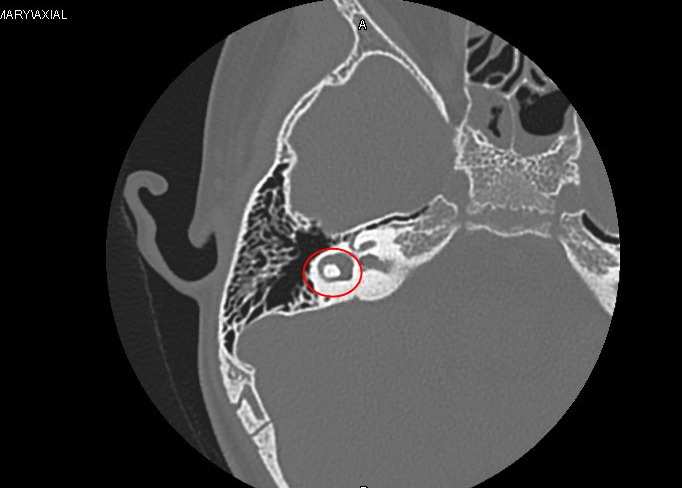

Tại đây, kết quả chụp CT xương thái dương bệnh nhi cho thấy có khối u xuất hiện ở mặt trong chuỗi xương con. Bệnh nhi được chẩn đoán mắc Cholesteatoma bẩm sinh.

Khối u trong tai bệnh nhi H. Ảnh: BVCC.